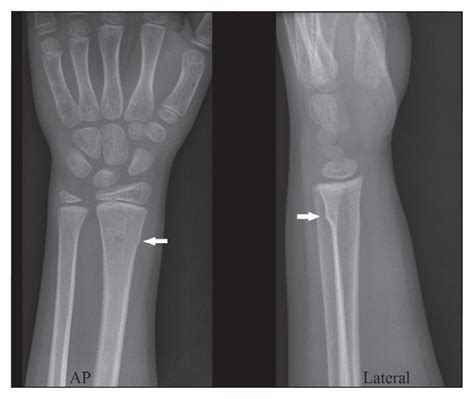

X-rays are the primary imaging tool used to diagnose a Buckle Fracture Radius. They provide a clear view of the bone and can show the characteristic buckling or compression of the bone.

• buckle fracture radius xray

• buckle fracture radius radiology